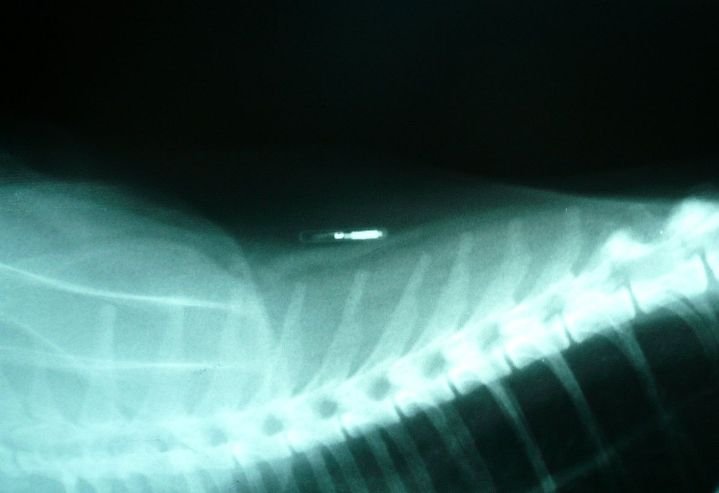

L’identification peut être réalisée par deux méthodes : la puce électronique (transpondeur) ou le tatouage. Dans les deux cas, seuls un vétérinaire ou un tatoueur agréé sont habilités à identifier votre animal.